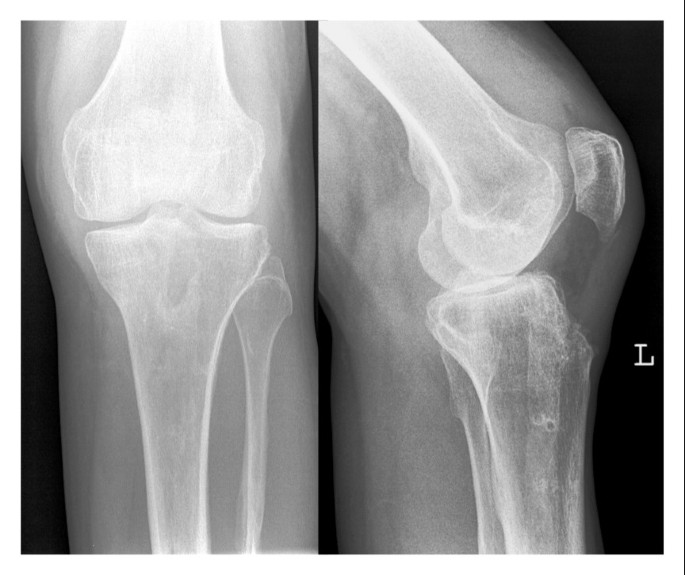

Effiziente Diagnostik Pathologischer Frakturen Sciencedirect